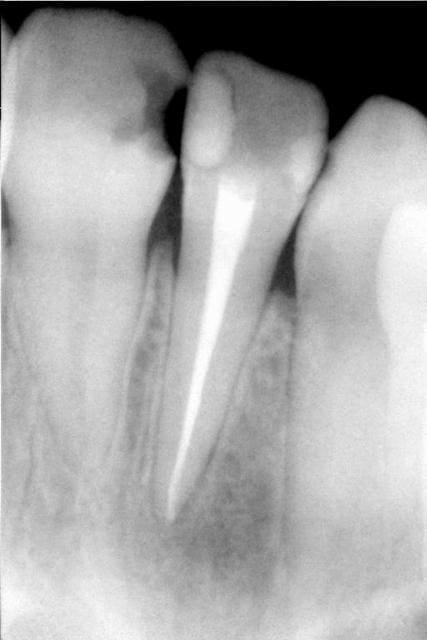

Ca peut etre aussi un artéfact de la radio pano qui est numérisée : hier j'en ai vue une avec des liserets noirs autour de tous les tenons radiculaires et il n'y a rien en pratique

mark, l'image que j'ai à la pano en natif est infiniment plus détaillée...4096 niveaux de gris au lieu des 256 donnés par la compression en format jpeg...c'est "le jour et la nuit"...

l'image radiologique d'un kyste est une lacune à contour régulier qui représente la paroi kystique et selon le contenu ( séreuse, pus...) la radioclarté varie

le granulome radiologiquement, a une image radio-claire arrondie, au contour généralement flou, ce qui le distingue du kyste qui possède une capsule périphérique et une image radiologique mieux délimitée et souvent plus volumineuse. Seul un examen anatomo-pathologique (après exérèse) permet toutefois de trancher sur la nature exacte de la lésion.

maintenant, je suis pas expert...mais on peut parfois voir la membrane kystique...tout dépend de son épaisseur...